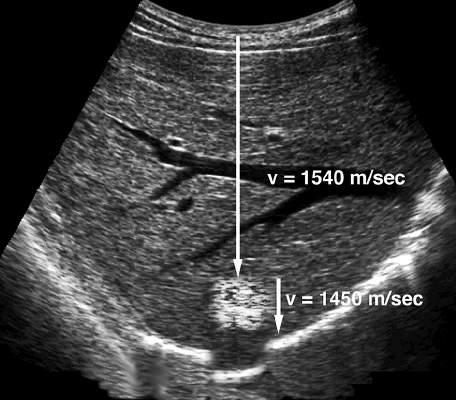

FIG. 1.3 Propagation Velocity Artifact. When sound passes through a lesion containing fat, echo return is delayed because fat has a propagation velocity of 1450 m/sec, which is less than the liver. Because the ultrasound scanner assumes that sound is being propagated at the average velocity of 1540 m/sec, the delay in echo return is interpreted as indicating a deeper target. Therefore the final image shows a misregistration artifact in which the diaphragm and other structures deep to the fatty lesion are shown in a deeper position than expected (simulated image).

Fig. 1.2 shows typical longitudinal propagation velocities for a variety of materials. In the body the propagation velocity of sound is assumed to be 1540 meters per second (m/sec). This value is the average of measurements obtained from normal soft tissue.2,3 Although this value represents most soft tissues, such tissues as aerated lung and fat have propagation velocities significantly less than 1540 m/sec, whereas tissues such as bone have greater velocities. Because a few normal tissues have propagation values significantly different from the average value assumed by the ultrasound scanner, the display of such tissues may be subject to measurement errors or artifacts (Fig. 1.3). The propagation velocity of sound (c) is related to frequency and wavelength by the following simple equation: c

propagation velocity of sound for the tissue is known. For example, if the time from the transmission of a pulse until the return of an echo is 0.000145 seconds and the velocity of sound is 1540 m/ sec, the distance that the sound has traveled must be 22.33 cm (1540 m/sec × 100 cm/m × 0.000145 sec = 22.33 cm). Because the time measured includes the time for sound to travel to the interface and then return along the same path to the transducer, the distance from the transducer to the reflecting interface is 22.33 cm/2 = 11.165 cm. By rapidly repeating this process, a two-dimensional (2-D) map of reflecting interfaces is created to form the ultrasound image. The accuracy of this measurement is therefore highly influenced by how closely the presumed velocity of sound corresponds to the true velocity in the tissue being observed (see Figs. 1.2 and 1.3), as well as by the important assumption that the sound pulse travels in a straight path to and from the reflecting interface.